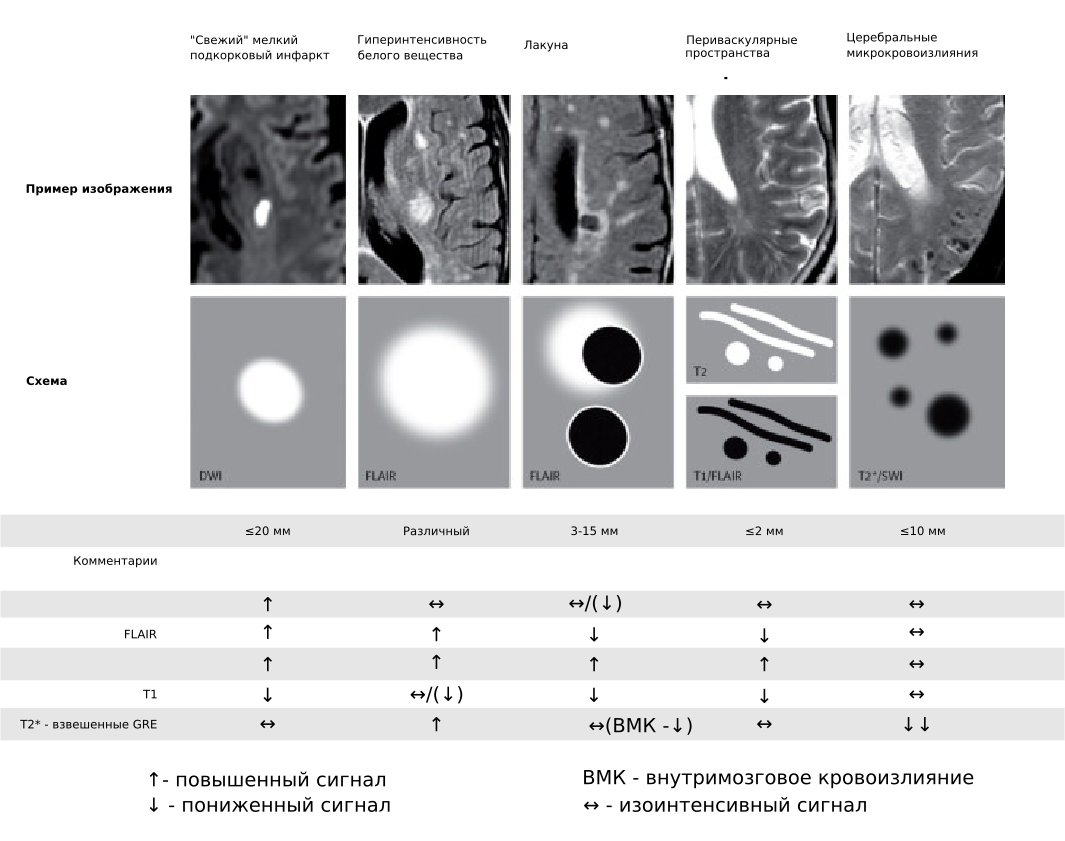

Fazekas grades. T1 t2 Flair. MRI t1 t2. T1 t2 мрт. T1 t2 fleur мрт.

Fazekas grades. T1 t2 Flair. MRI t1 t2. T1 t2 мрт. T1 t2 fleur мрт.

Fazekas grades. MRI t1 t2. Шкала Фазекас мрт. Очаги Фазекас мрт.

Fazekas grades. MRI t1 t2. Шкала Фазекас мрт. Очаги Фазекас мрт.

Fazekas grades. Инсульт на Dwi. Лейкоареоз Фазекас. Инсульт Dwi Flair несоответствие. Brain stroke MRI.

Fazekas grades. Инсульт на Dwi. Лейкоареоз Фазекас. Инсульт Dwi Flair несоответствие. Brain stroke MRI.

Fazekas grades. Фазекас мрт. Фазекас 2 мрт. Fazekas Scale MRI.

Fazekas grades. Фазекас мрт. Фазекас 2 мрт. Fazekas Scale MRI.